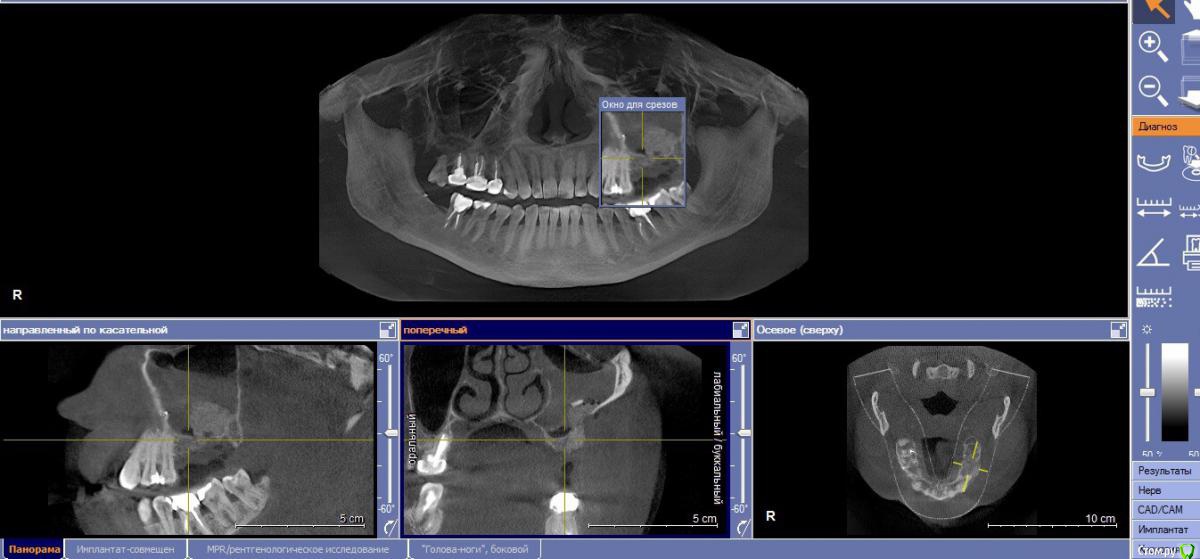

Кариес+ Опубликовано 27 августа, 2016 Поделиться Опубликовано 27 августа, 2016 Подготовили перед операцией кт , оказалось 15го года, не обратил внимание, пазуха была чиста . После операции сделал кт , а там пазуха полная и с синусом прокосячил . Что ожидать коллеги, как спасти ситуацию Ссылка на комментарий

Bier Опубликовано 27 августа, 2016 Поделиться Опубликовано 27 августа, 2016 В пазухе отек, а вот кость придется добавлятьА что за инородное тело на 3м снимке? Ссылка на комментарий

Кариес+ Опубликовано 27 августа, 2016 Автор Поделиться Опубликовано 27 августа, 2016 Да это кортикалка , оттек может быть связак с моим вмешательством? Это может быть кровь или физ.раствор от пьезотома? Если предположить что я прорвал синус Ссылка на комментарий

Доктор Добрых Дел Опубликовано 27 августа, 2016 Поделиться Опубликовано 27 августа, 2016 Это не жидкость. Отек слизистой. Думаю материал в кость вряд ли превратится так как с костью практически не контактирует, так что лучше сразу убрать и переделать. Ссылка на комментарий

колесников Опубликовано 27 августа, 2016 Поделиться Опубликовано 27 августа, 2016 Дайте мне надежду в которую я буду верить))Ну отёк может и сойдёт,только синуслифтинг не удался. Отслоили недостаточно,весь графт на щёчной стенке остался. Ждать смысла нет. 4 Ссылка на комментарий